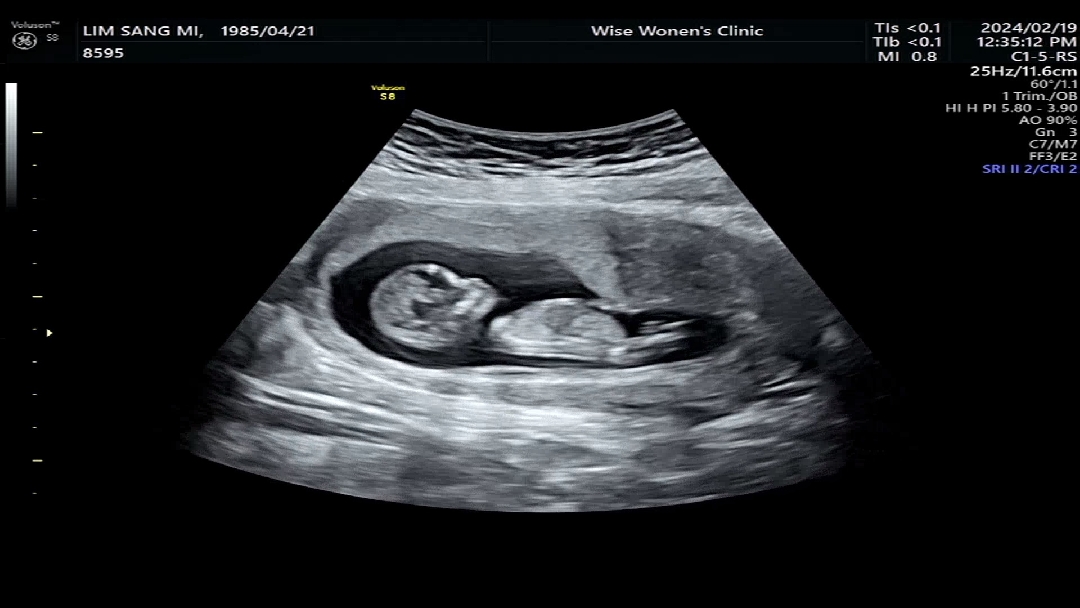

성별 예측해주세요~

서벅지에가려서 영 알아볼수가없고 각도법을 어떻게봐야할지 모르겠어요~ 고수님들 알려주세요~